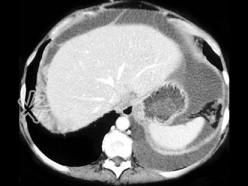

- 女,36岁, 肝区不适数月,CT检查如图